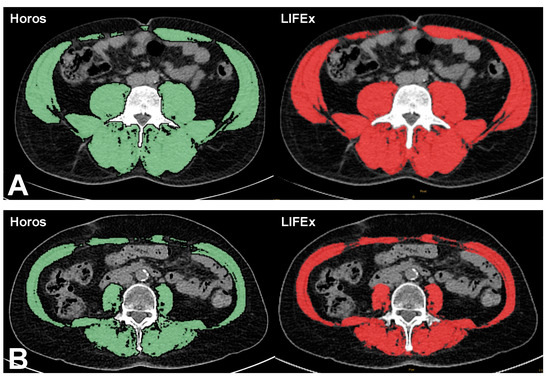

2.4. Muscle Mass Evaluation

2.5. LIFEx

2.6. Horos

3.2. Muscle Area

| Muscle mass (cm2) | 132 ± 37 | 131 ± 37 |